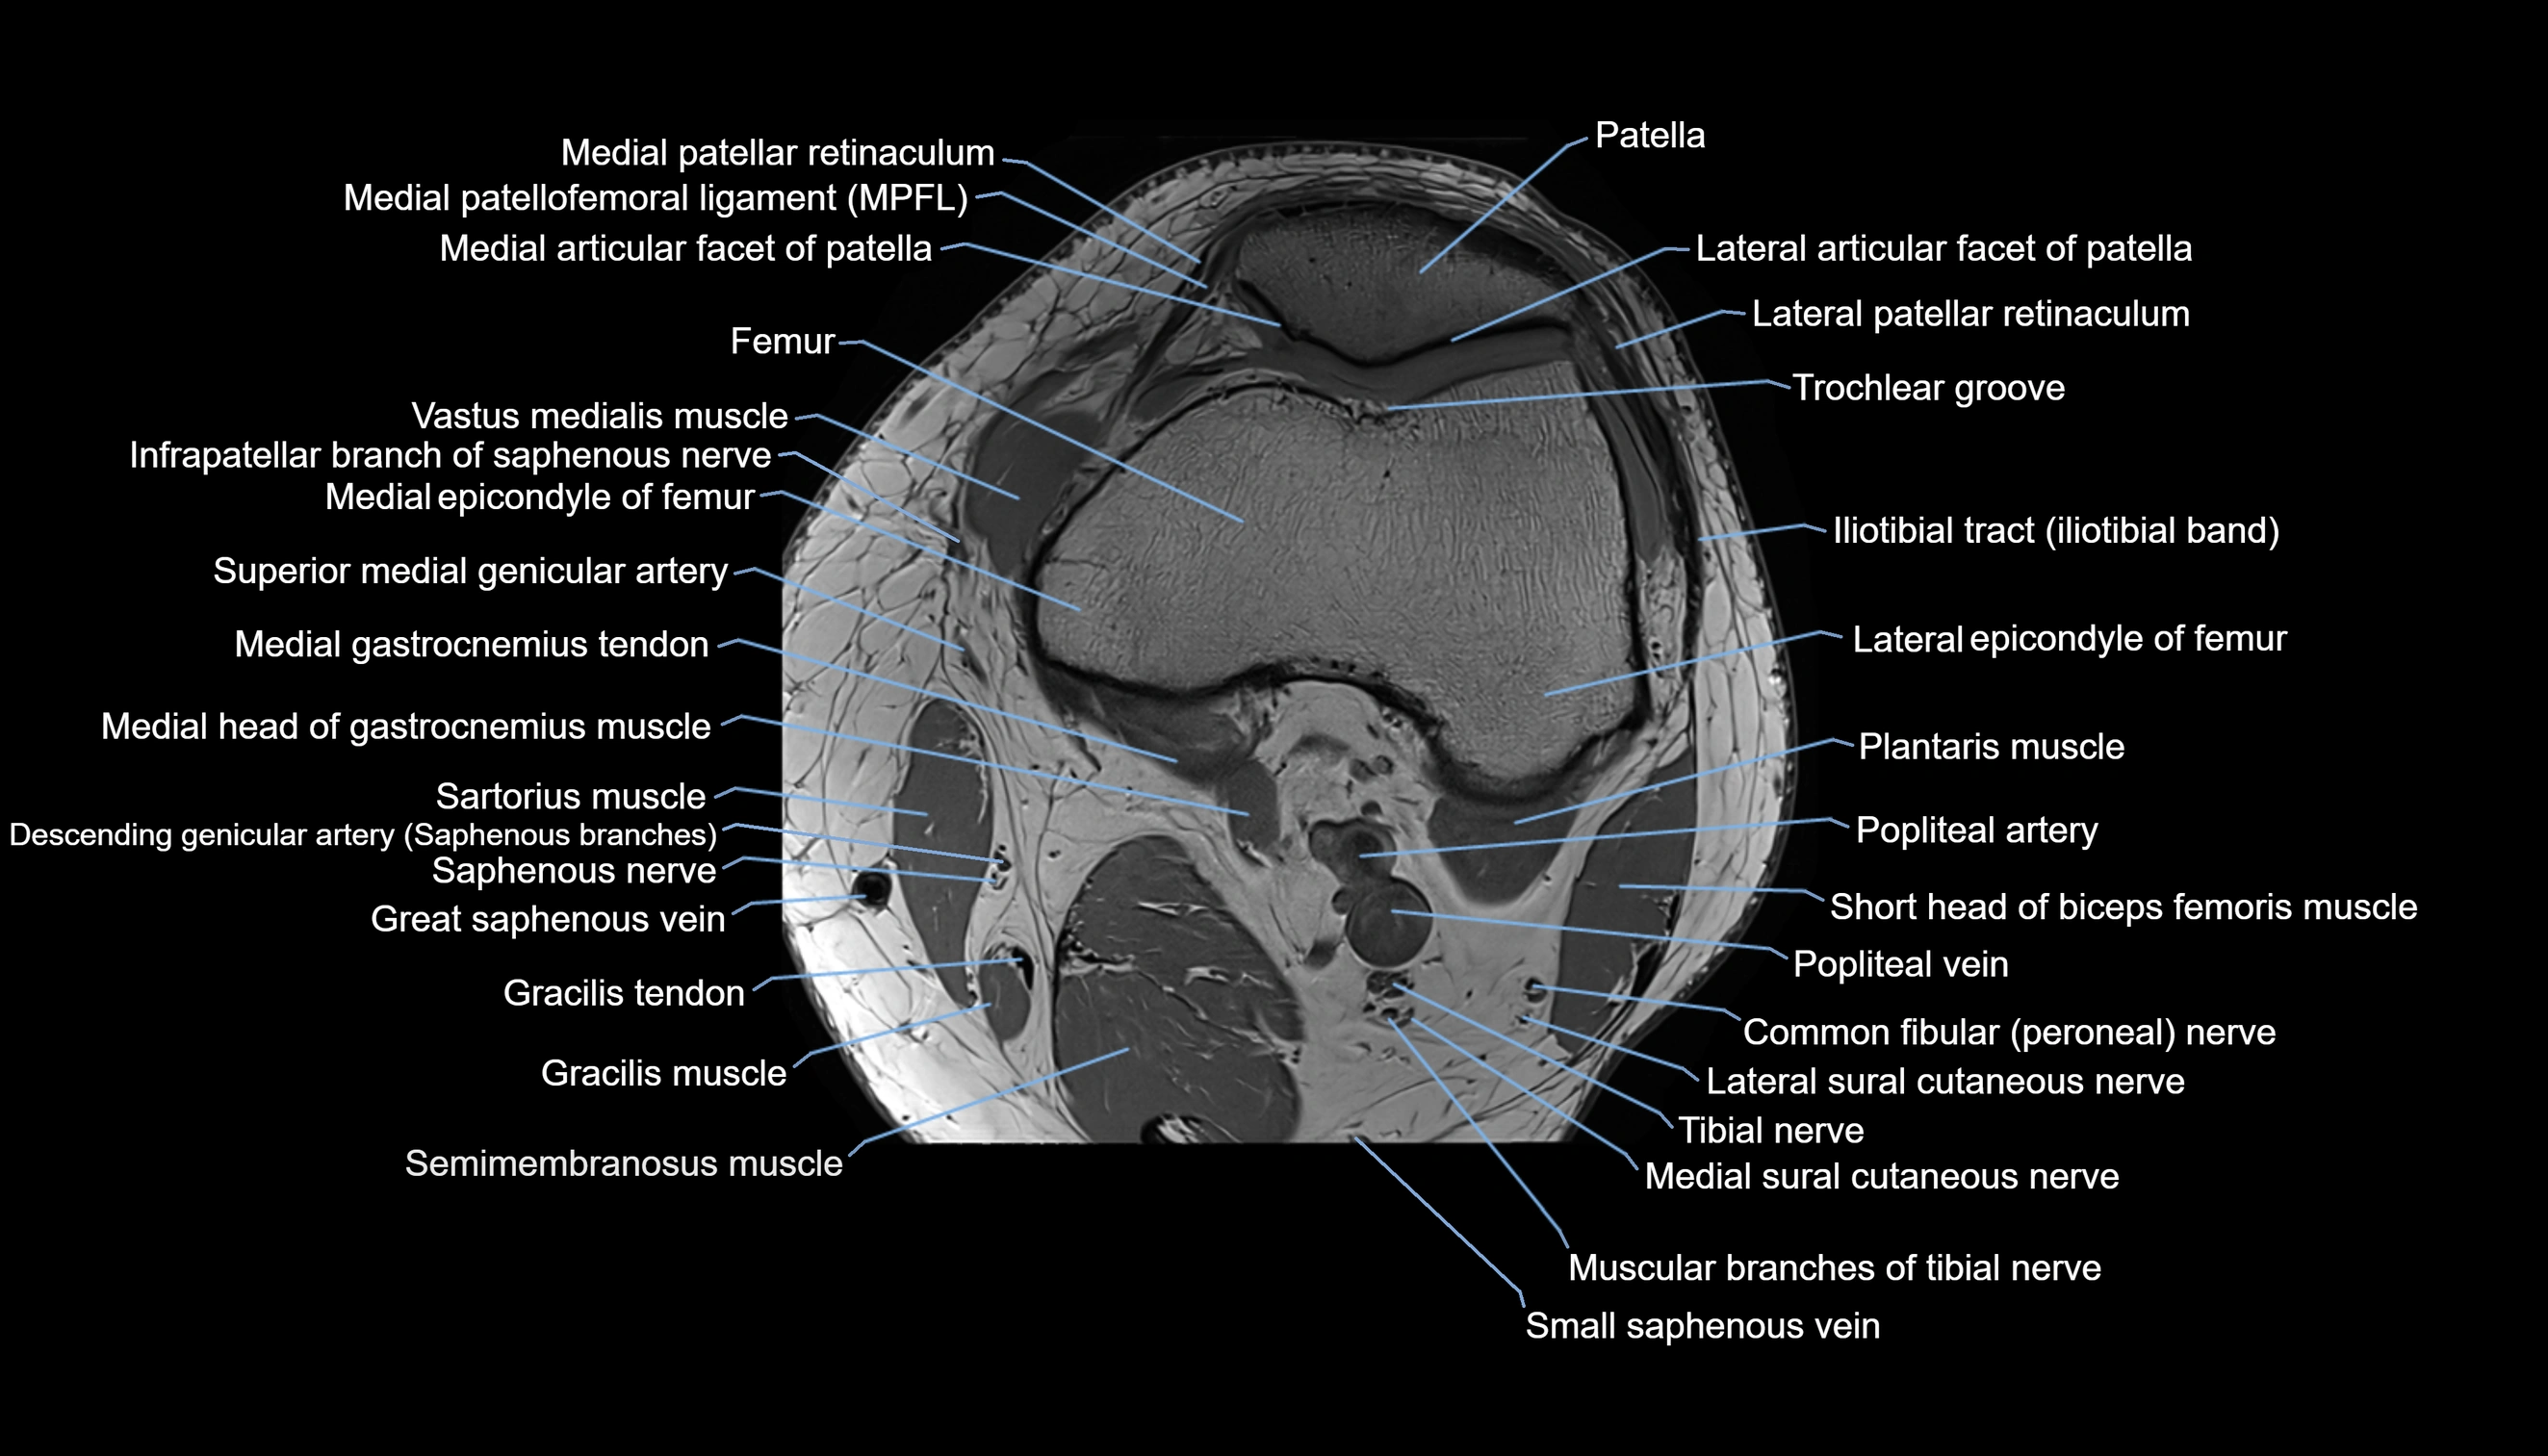

- Knee Joint

- Lateral articular facet of patella

- Lateral border of patella

- Lateral patellar retinaculum

- Lateral patellofemoral ligament

- Medial articular facet of patella

- Medial border of patella

- Medial epicondyle of femur

- Medial gastrocnemius tendon

- Medial head of gastrocnemius muscle

- Medial patellar retinaculum

- Medial patellofemoral ligament

- Medial sural cutaneous nerve

- Muscular branches of tibial nerve

- Patella

- Patellar articular cartilage

- Popliteal artery

- Popliteal lymph nodes

- Popliteal vein

- Saphenous nerve

- Sartorius muscle

- Semimembranosus muscle

- Small saphenous vein

- Superior medial genicular artery

- Tibial nerve

- Trochlear groove

- Vastus medialis muscle

- great saphenous vein